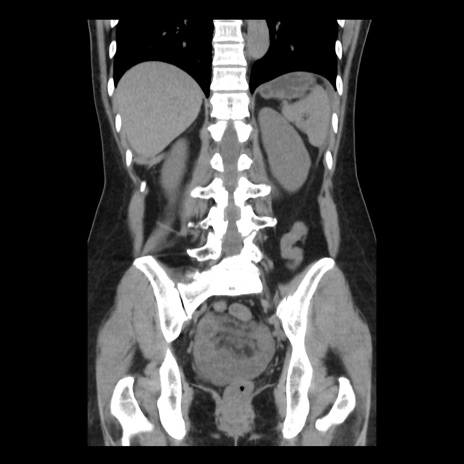

症例10(冠状断像)

【症例】 50歳代女性

【主訴】 腹痛

【現病歴】前日生レバーを食べた。今朝に排便あり。 昼前に突然発症の腹痛を生じ、当院救急外来を受診した。

【既往歴】 子宮筋腫にてで子宮全摘後

【身体所見】 意識清明、腹部:平坦、軟、下腹部やや左を中心に圧痛・反跳痛あり、筋性防御あり

【データ】WBC 7800、CRP 0.07